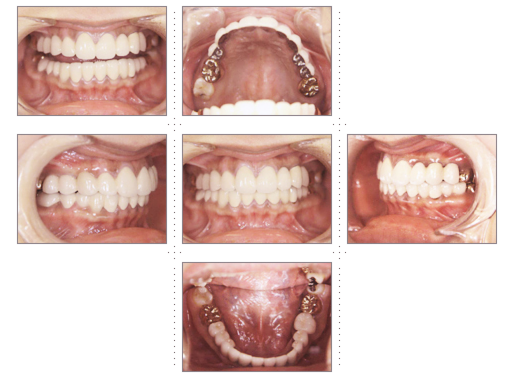

症例2

主婦 33才 女性

上下顎とも乳歯が残っており歯と歯の隙間が気になり、歯並びを奇麗にしたいとのご希望でした。

術後、家族や友人からもキレイになったと言われ、ご本人もご自分の歯のように気に入っていただけました。原因不明な頭痛もなくなり、快適な生活を送っていらっしゃいます。